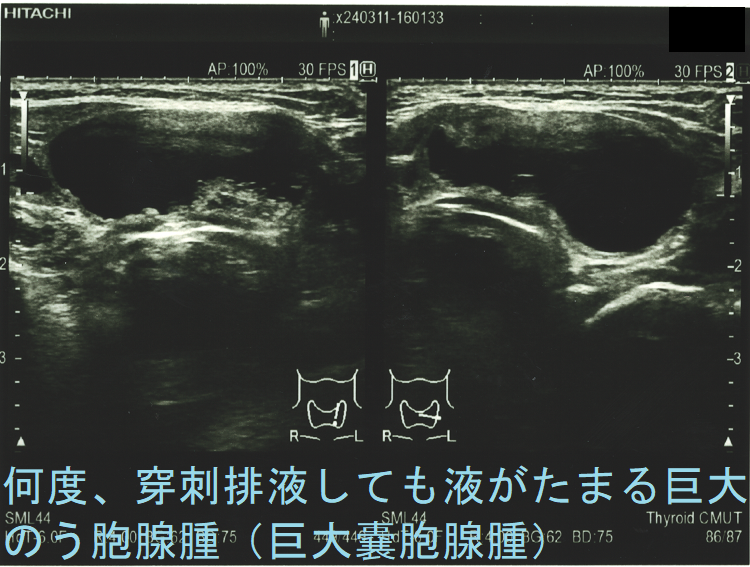

甲状腺癌と確定できない、または癌ではない甲状腺腫瘍の手術適応は①4cm以上(相対的適応)②増大傾向(甲状腺癌を否定できない、増大傾向の腺腫様甲状腺腫は約3%、濾胞性腫瘍は約18%が癌)③血中サイログロブリン値1000ng/mL以上(甲状腺癌を否定できない、甲状腺乳頭癌では有用性なく甲状腺乳頭癌を除くと46%が甲状腺濾胞癌)④超音波エコー検査・細胞診で甲状腺癌を完全に否定できない⑤気管食道などを圧迫、息しにくい、飲み込みにくい⑥縦隔内進展⑦美容上の問題(首が腫れている)⑧何度、穿刺排液しても液がたまる巨大のう胞腺腫(巨大嚢胞腺腫)。

- (良性)のう胞腺腫(嚢胞腺腫)[単に、のう胞(嚢胞)と呼ばれる事が多い]で、気管食道などを圧迫し、息がしにくい・飲み込みにくいなどに加え、穿刺排液困難や何度、穿刺排液してもすぐに液がたまる巨大のう胞腺腫(巨大嚢胞腺腫)

頻回に穿刺排液しても液がたまる巨大のう胞腺腫(巨大嚢胞腺腫)は、良性腫瘍(のう胞型濾胞腺腫:嚢胞型濾胞腺腫)であっても手術適応になります。単に、のう胞(嚢胞)と呼ばれる事も多いですが、甲状腺組織の破壊・変性によるのう胞変性(嚢胞変性)でなく、れっきとした腫瘍です。

頻回に穿刺排液しても、

なら、内分泌外科に甲状腺部分切除(半葉切除が多い)を依頼します。

ケース② 巨大過ぎる甲状腺のう胞腺腫(甲状腺嚢胞腺腫) 8 cm以上